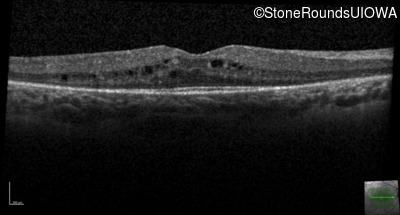

Age at visit: 7 years

This 7 year old girl has had very poor vision in dim light and slightly subnormal acuity her entire life.

Age at visit: 7 years (Visit 2)

Age at visit: 8 years

Age at visit: 9 years

Age at visit: 10 years

Age at visit: 12 years

Age at visit: 13 years

Age at visit: 14 years

Age at visit: 15 years

Age at visit: 16 years

Age at visit: 17 years

Age at visit: 19 years

Age at visit: 21 years